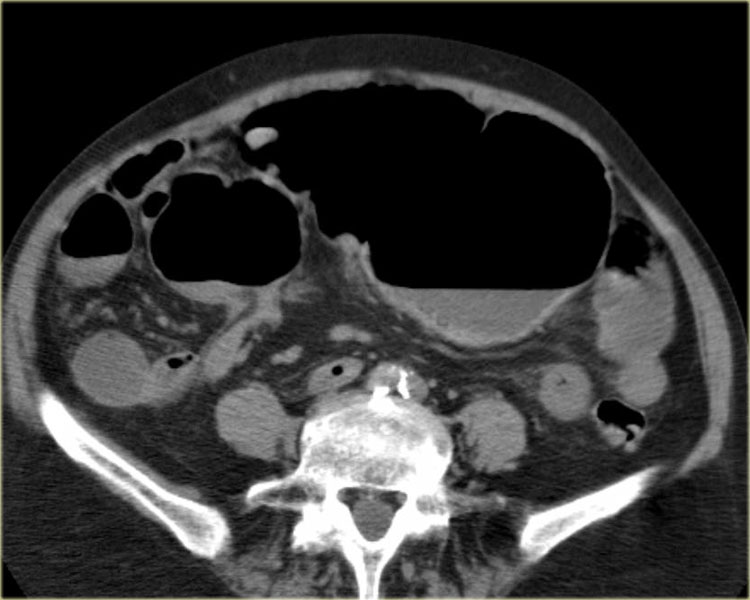

Bên trái là các hình ảnh CT bổ sung của cùng bệnh nhân nêu trên.

Hãy quan sát các hình ảnh này, tìm kiếm các dấu hiệu chính rồi tiếp tục.

Đầu tiên, chúng ta thấy đại tràng xuống xẹp và đại tràng lên không giãn, do đó đây không thể là xoắn đại tràng sigma.

Thứ hai, chúng ta thấy một cấu trúc hình mỏ chim ở góc phần tư dưới bên phải, đây là vị trí xoắn của ruột.

Ở góc phần tư dưới bên trái, chúng ta thấy manh tràng giãn.